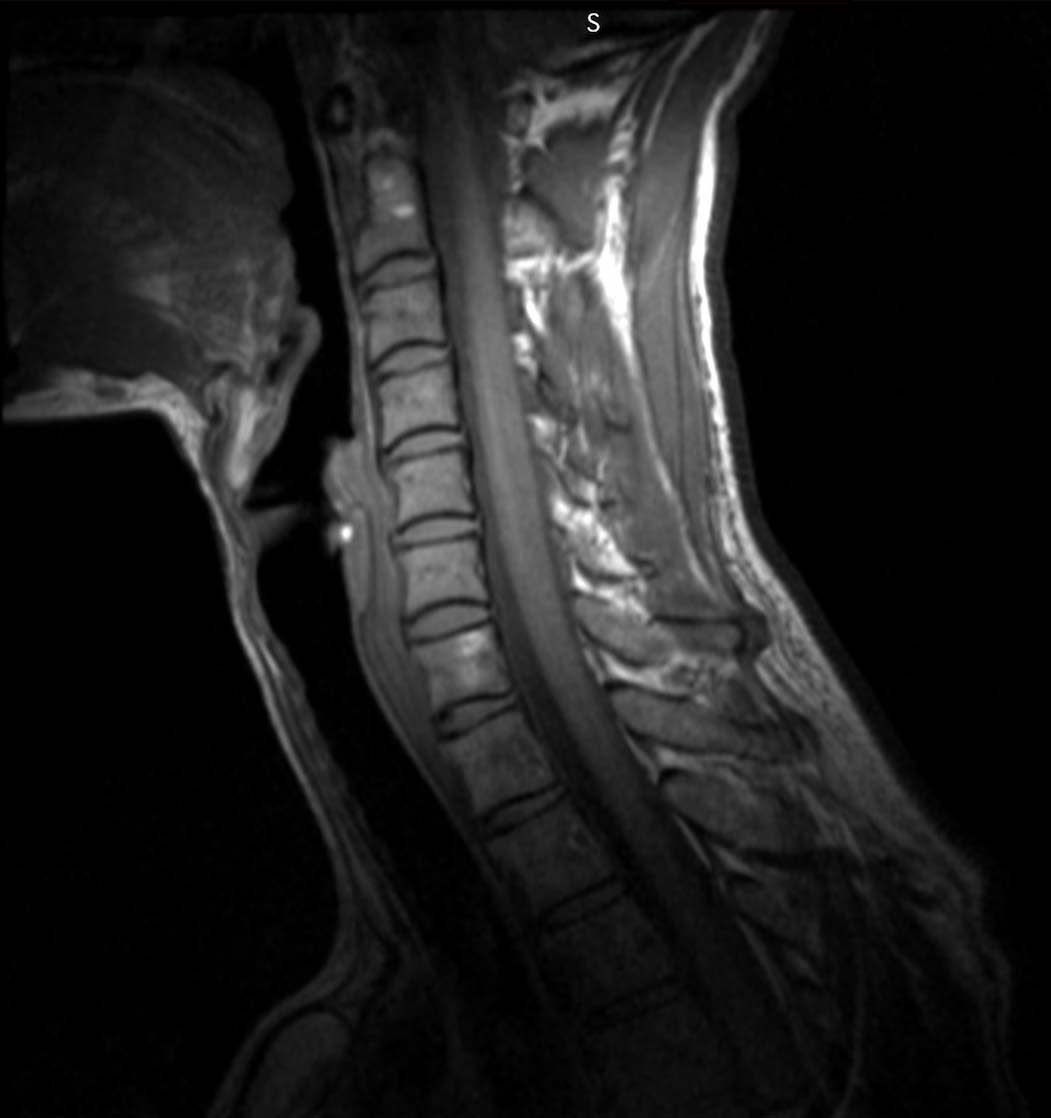

Under the guidance of Professor Ana Arias and Professor Miki Lustig, Zamarayeva created patient-specific coils for evaluating health conditions involving the neck that can, for example, detect spine lesions (Figure 2). The coils she created enhance the signal-to-noise ratio by bringing antennas as close as possible to the patient, resulting in higher resolution MRIs. With the unique combination of design freedom and high-temperature materials, the Carbon DLS process was able to make this innovation possible.

The researchers used the new digitally manufactured cervical collar and surface coil combination to acquire MRI images of test phantoms and a human subject. In the test done of MRI phantoms (a simple structure to ease analysis, not shown here), there was significant improvement of signal-to-noise ratios of the patient-specific coil images (Figure 4).

The excellent signal-to-noise ratio is noted by the high dynamic range of contrast in both T1 and T2 weighted images above. This enhanced resolution is critical for improved diagnosis and for more accurate procedure planning. Some improved diagnoses could include the visualization of tumors or the detection of plaque accumulation in the carotid artery, which can lead to a stroke.